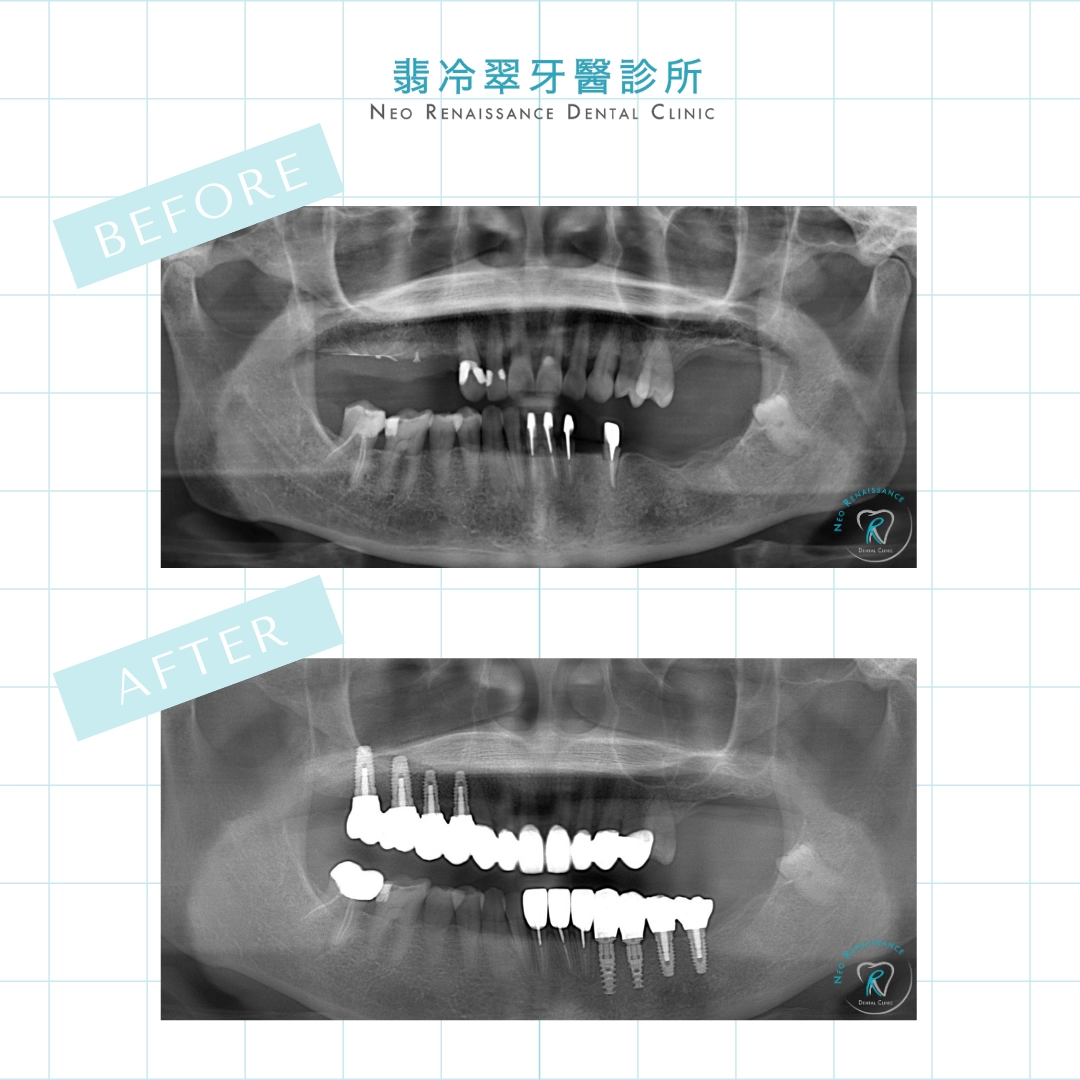

患者:徐小姐

療程:全口重建

而後續陳醫師也發現

患者後牙有大範圍的缺牙及牙齒磨耗嚴重的問題

慢慢地將患者的牙齒重建起來!![]()

還給徐小姐一口仿真度極高又耐用的牙齒